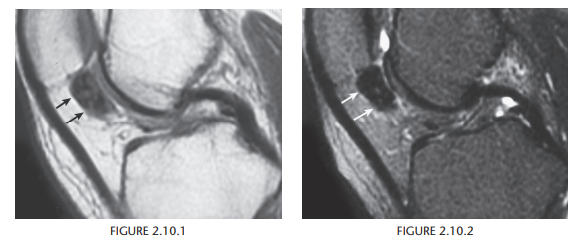

Medial meniscal cyst

Osteochondritis dissecans (osteochondrosis) of the medial femoral condyle

An osteochondral fracture that was initially caused by shearing, rotatory, or

tangentially aligned impaction forces

semicircular lucency, with an adjacent bony fragment,

on the lateral aspect of the medial femoral condyle

(arrows)

Encircling fluid or focal cystic areas between the medullary canal and the fragment on MRI suggests a potentially loose or unstable fragment.